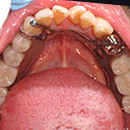

この患者様は、数十年間歯科治療を受けた事がなく、痛い時はじっと我慢をし、そのうちに何本か抜けてしまったそうです。

もちろん入れ歯を入れた事もありません。

この状態でもどうにか食べる事は出来たようですが、家族の強いすすめもあって意を決して来院されました。来院された時は、残存歯16本中、13本が歯の頭 の部分(歯冠部)は崩壊し、根だけが残っている(残根)状態でした。虫歯と歯周病の進行状態から上顎は6本、下顎は3本の歯が抜歯となりました。

残り少ない歯に直接バネ(クラスプ)をかけると、負担が強く、歯がグラグラになってしまうので、あえて歯冠部を切断し、その上に義歯をかぶせる、いわゆる総入れ歯(残根上総義歯)にしてしまします。

本症例では、総義歯の安定のため、下顎の3本の歯にはマグネットをつけました。